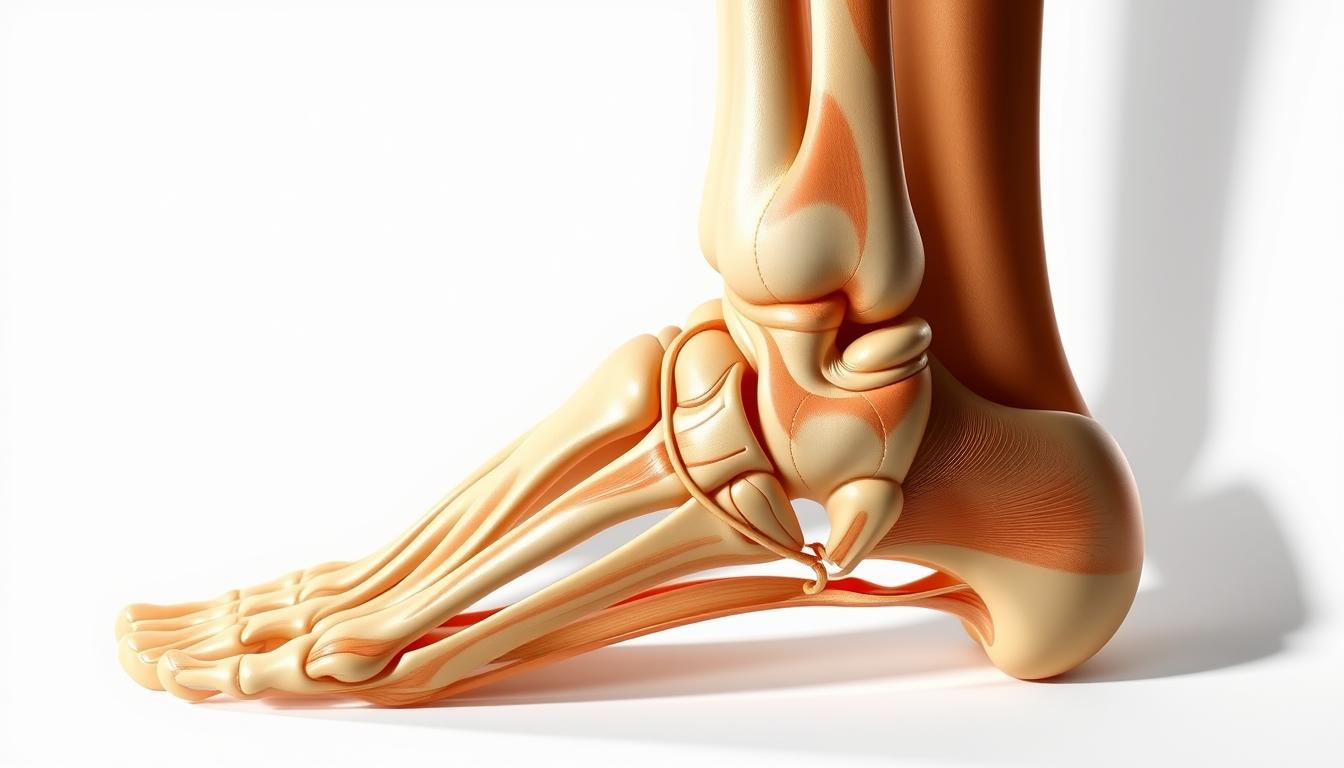

Understanding the dorsolateral view of the left foot and ankle is key for medical experts and those interested in foot anatomy. The foot’s structure is complex, with many bones, muscles, and ligaments. It’s both fascinating and challenging to study.

The dorsolateral view gives a special look at the foot’s structure. It shows how all parts work together. This view helps us understand the foot’s complexity and its role in our daily movements.

The dorsolateral view shows the foot from the top and outer side. It’s key for seeing how foot bones fit together with muscles and ligaments. This view helps us understand the foot’s complex design.

In clinics, the dorsolateral view is very important for diagnosing and treating foot issues. It helps doctors check if the foot structure is right. This view is key for spotting problems like fractures, sprains, and tendon injuries.

Understanding the anatomical perspective of the foot helps doctors make accurate diagnoses and treatment plans. The dorsolateral view is a big part of this, giving a detailed look at the foot’s anatomy.